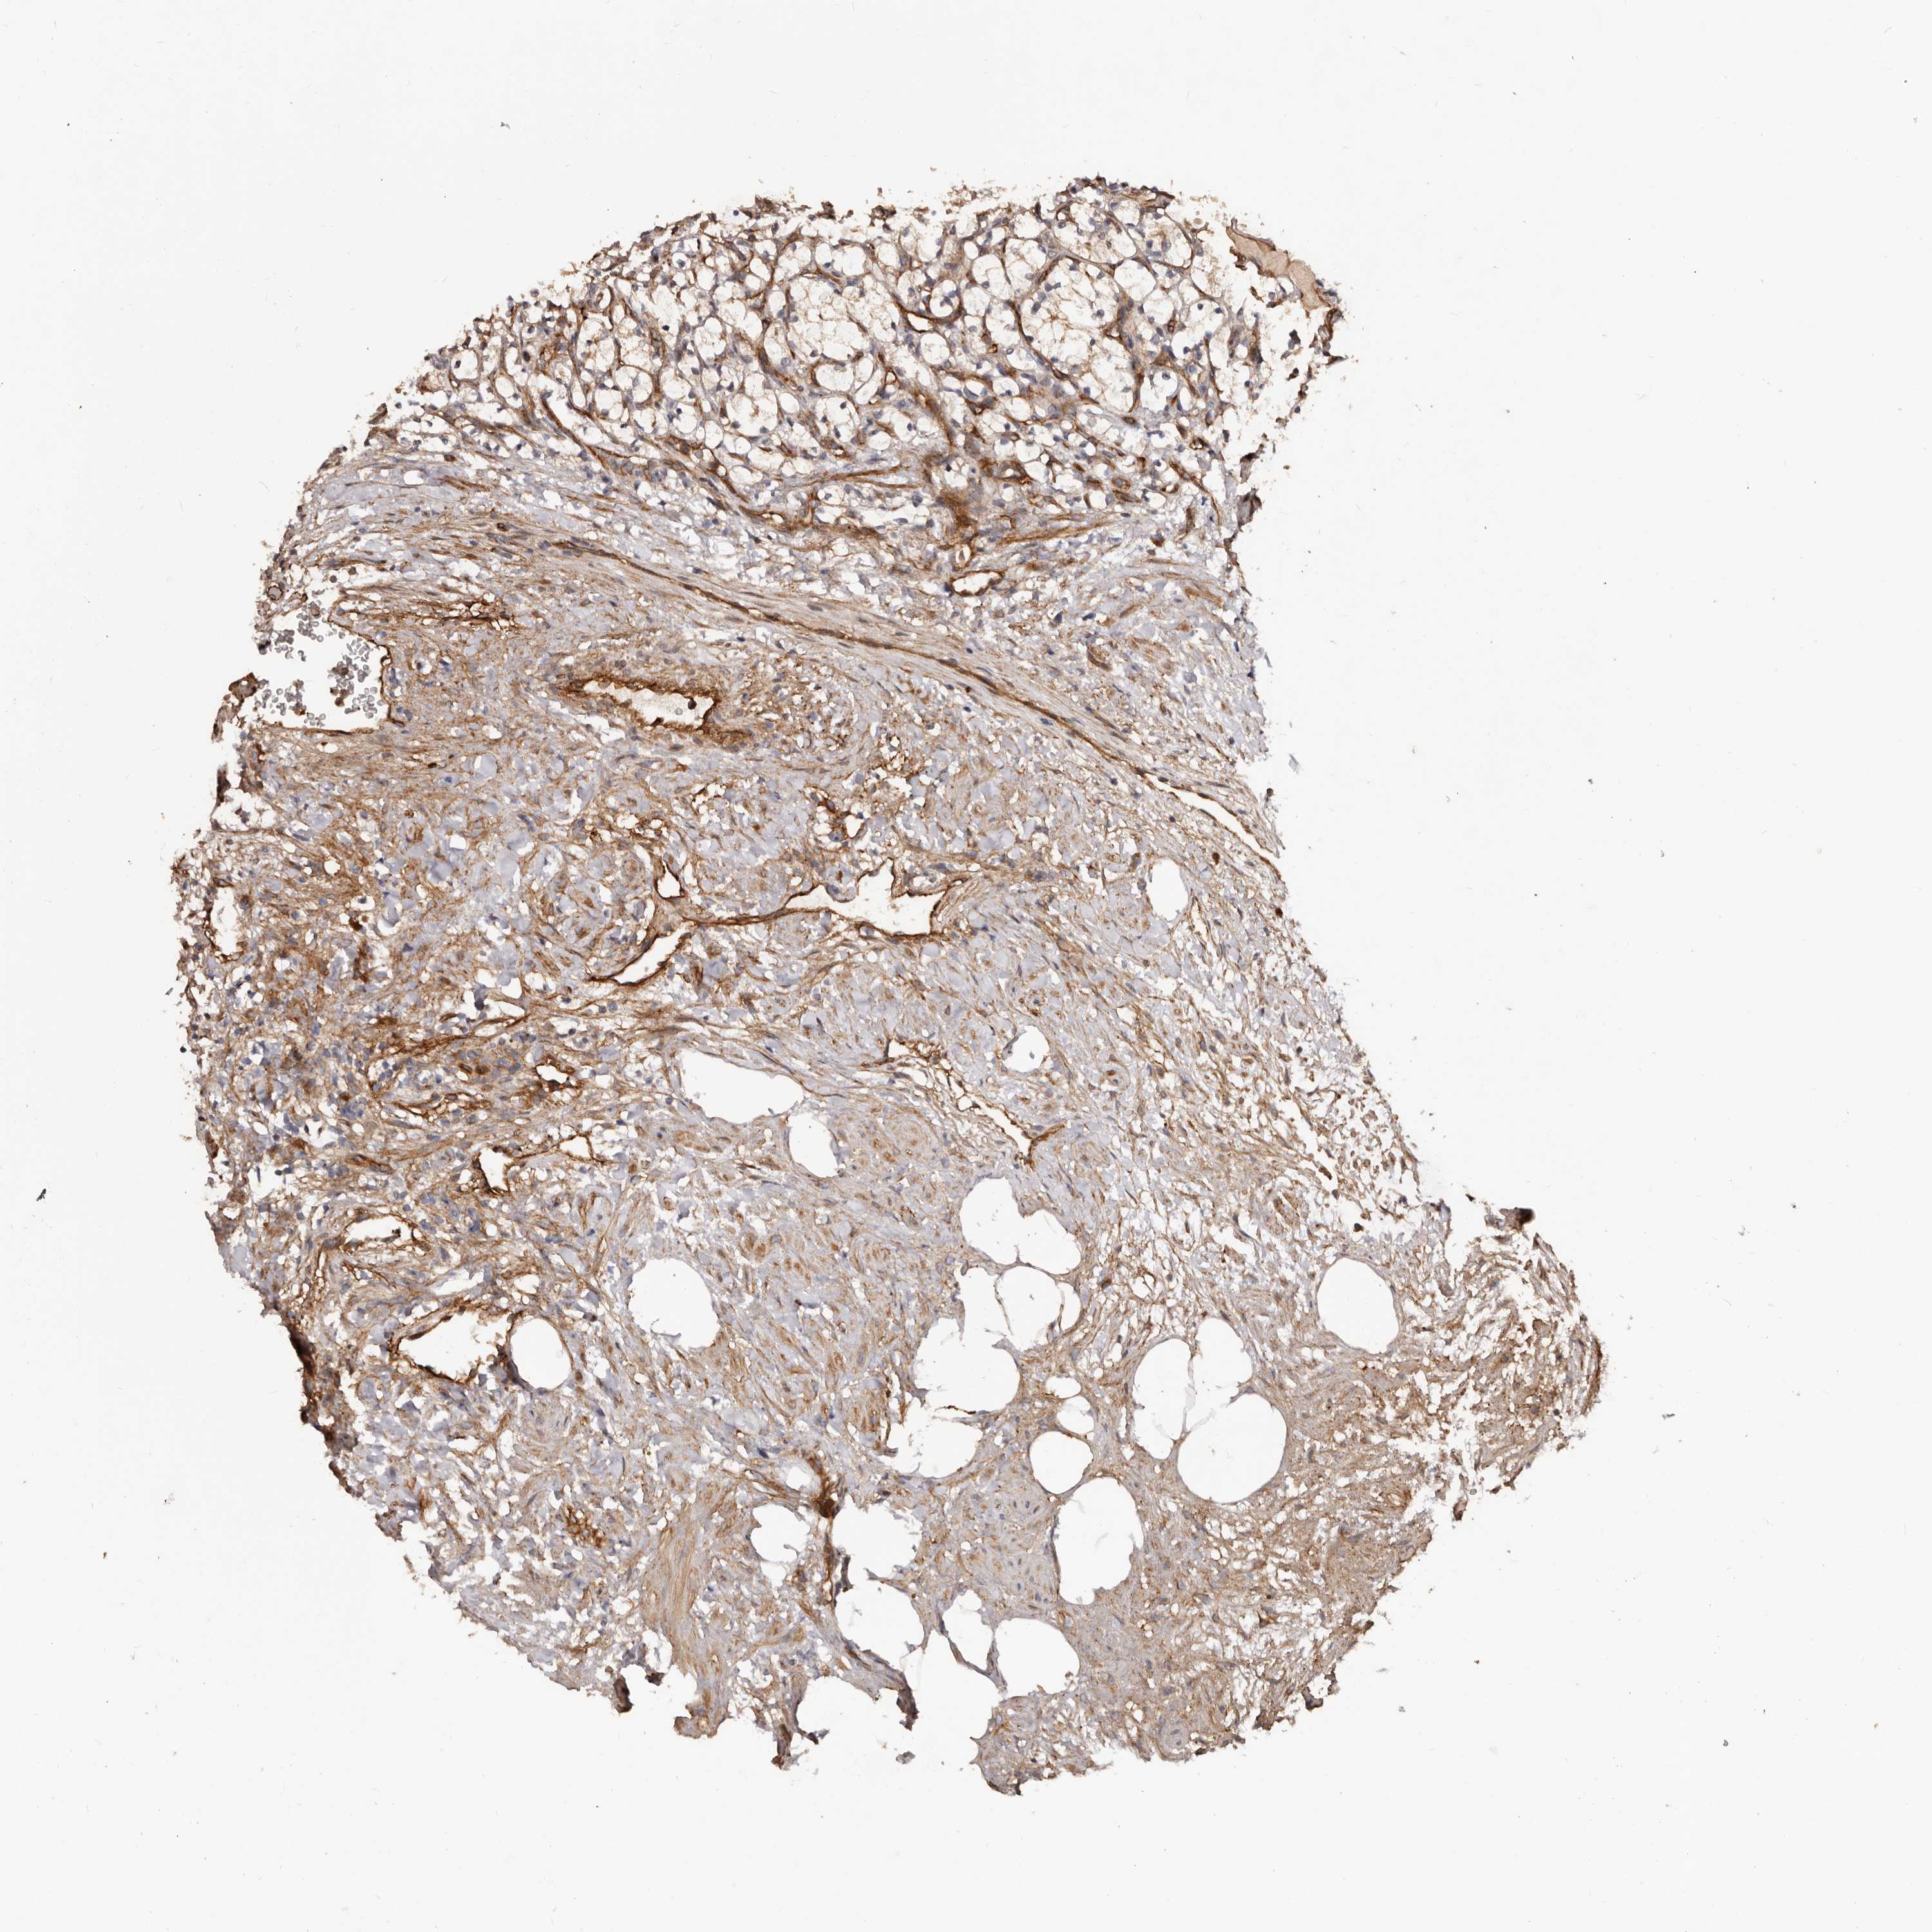

KIDNEY RENAL PAPILLARY CELL CARCINOMA (TCGA) - Interactive survival scatter ploti

The Survival Scatter plot shows the clinical status (i.e. dead or alive) for all individuals in the patient cohort, based on the same data that underlies the corresponding Kaplan-Meier plots. Patients that are alive at last time for follow-up are shown in blue and patients who have died during the study are shown in red.

The x-axis shows the expression levels (FPKM) of the investigated gene in the tumor tissue at the time of diagnosis. The y-axis shows the follow-up time after diagnosis (years). Both axes are complimented with kernel density curves demonstrating the data density over the axes. The top density plot shows the expression levels (FPKM) distribution among dead (red) and alive patients (blue). The right density plot shows the data density of the survived years of dead patients with high and low expression levels respectively, stratified using the cutoff indicated by the vertical dashed line through the Survival Scatter plot. This cutoff is automatically defined based on the FPKM cutoff that minimizes the p-score. The cutoff can be changed by dragging the vertical line or by entering a cutoff value in the square labeled "Current cut-off".

Under the Survival Scatter plot the p-score landscape (black curve; left axis) is shown together with dead median separation (red curve; right axis). Dead median separation is the difference in median mRNA expression between patients who have died with high and low expression, respectively. It is calculated as follows: median FPKM expression of dead patients with high expression - median FPKM expression of dead patients with low expression. This is intended to aid the user in visually exploring custom cutoffs and the associated p-scores and dead median separation.

Individual patient data is displayed and can be filtered by clicking on one or more of the category buttons on the top of the page. Categories describing expression level and patient information include: high, low, alive, dead, female, male and tumor stages. The scale of the x-axis can be toggled between linear and log-scale by clicking on the "x log" button. Mouse-over function shows TCGA ID, patient information and mRNA expression (FPKM) for each patient.

& Survival analysisi

Kaplan-Meier plots summarize results from analysis of correlation between mRNA expression level and patient survival. Patients were divided based on level of expression into one of the two groups "low" (under cut off) or "high" (over cut off). X-axis shows time for survival (years) and y-axis shows the probability of survival, where 1.0 corresponds to 100 percent.

GTPBP1 is not prognostic in Kidney Renal Papillary Cell Carcinoma (TCGA)

Best expression cut offi

Based on the FPKM value of each gene, patients were classified into two groups and association between prognosis (survival) and gene expression (FPKM) was examined. The best expression cut-off refers the FPKM value that yields maximal difference with regard to survival between the two groups at the lowest log-rank P-value. Best expression cut-off was selected based on survival analysis .

When clicking on this number, the vertical dashed line indicating cut-off, the interactive survival plot, and the Kaplan-Meier curve will be adjusted to show results based on the best expression cut-off.

: 13.29